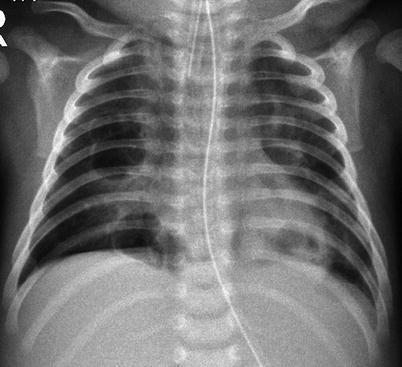

Children represent 2 % of the reported cases of human immunodeficiency virus (HIV) infection. Most children are infected after vertical transmission from their mother, and majority develop acquired immunodeficiency syndrome (AIDS) early in life. There is increased susceptibility to bacterial, viral, fungal, protozoal, and opportunistic infections. Lobar or segmental consolidations are the most common patterns (Marks et al. 1996). Mycobacterial infection can be seen in AIDS patients, and the radiographic appearance mimics that seen in immunocompetent children with primary tuberculosis. Mycobacterium avium-intracellulare is also encountered later in the course of disease and imaging findings cannot be distinguished with other forms of mycobacterial infections (Collingsworth 2005). Pneumocystis jiroveci is the most common opportunistic pulmonary infection in children with AIDS, occurring in up to 50 %, and is the leading pulmonary cause of death (Jeanes and Owens 2002). Radiographic appearances are variable and include hyperinflation with diffuse bilateral interstitial or nodular infiltrates from the perihilar region to the periphery, which often progresses to widespread alveolar opacities with air bronchogram (Fig. 13.30). Cavitary nodules and cysts can be seen, with pneumothorax and/or pneumomediastinum as common complications. HRCT findings include patchy or diffuse ground-glass opacity, consolidation, cyst or cavities, centrilobular opacities, nodules, peribronchial cuffing, and interlobular septal thickening (Jeanes and Owens 2002; Collingsworth 2005).

Fig. 13.30.

Pneumocystis jiroveci infection. Radiograph of a 10-month-old boy diagnosed with severe combined immune deficiency syndrome showing diffuse reticulonodular interstitial pattern in both lungs with development of lung consolidations (a). Radiograph of a 14-month-old girl with HIV infection showing diffuse, bilateral interstitial lung pattern extending from the hilum (b). There is a cyst noted on the peripheral right lung (arrow)